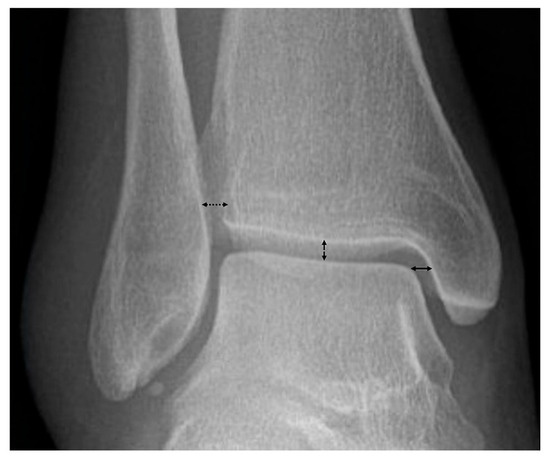

- Gibson, P.D.; Ippolito, J.A.; Hwang, J.S.; Didesch, J.; Koury, K.L.; Reilly, M.C.; Adams, M.; Sirkin, M. Physiologic widening of the medial clear space: What’s normal? J. Clin. Orthop. Trauma 2019, 10, S62–S64. [Google Scholar] [CrossRef]

- Hermans, J.J.; Wentink, N.; Beumer, A.; Hop, W.C.; Heijboer, M.P.; Moonen, A.F.; Ginai, A.Z. Correlation between radiological assessment of acute ankle fractures and syndesmotic injury on MRI. Skelet. Radiol. 2012, 41, 787–801. [Google Scholar] [CrossRef]

- Lau, B.C.; Allahabadi, S.; Palanca, A.; Oji, D.E. Understanding Radiographic Measurements Used in Foot and Ankle Surgery. J. Am. Acad. Orthop. Surg. 2022, 30, e139–e154. [Google Scholar] [CrossRef]

- Krähenbühl, N.; Weinberg, M.W.; Davidson, N.P.; Mills, M.K.; Hintermann, B.; Saltzman, C.L.; Barg, A. Imaging in syndesmotic injury: A systematic literature review. Skelet. Radiol. 2018, 47, 631–648. [Google Scholar] [CrossRef]

- DeAngelis, J.P.; Anderson, R.; DeAngelis, N.A. Understanding the superior clear space in the adult ankle. Foot Ankle Int. 2007, 28, 490–493. [Google Scholar] [CrossRef]